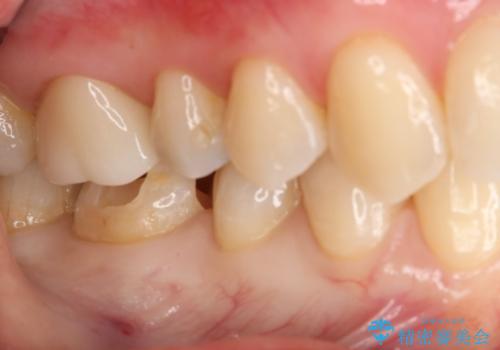

銀の詰め物が取れた セラミックインレー治療

- 右下6番のメタルインレー脱離のため来院。

セラミックの治療を希望されたため切削量を考慮し、セラミックインレーでの治療を選択しました。

う蝕が深くまで進行していたので、CRで裏層した上で形成・印象をしています。